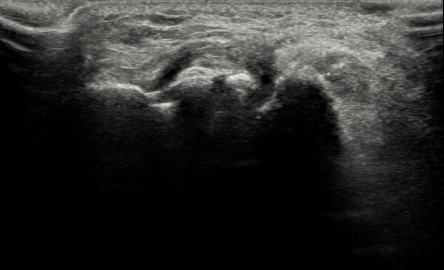

수술 후

2022.09.20